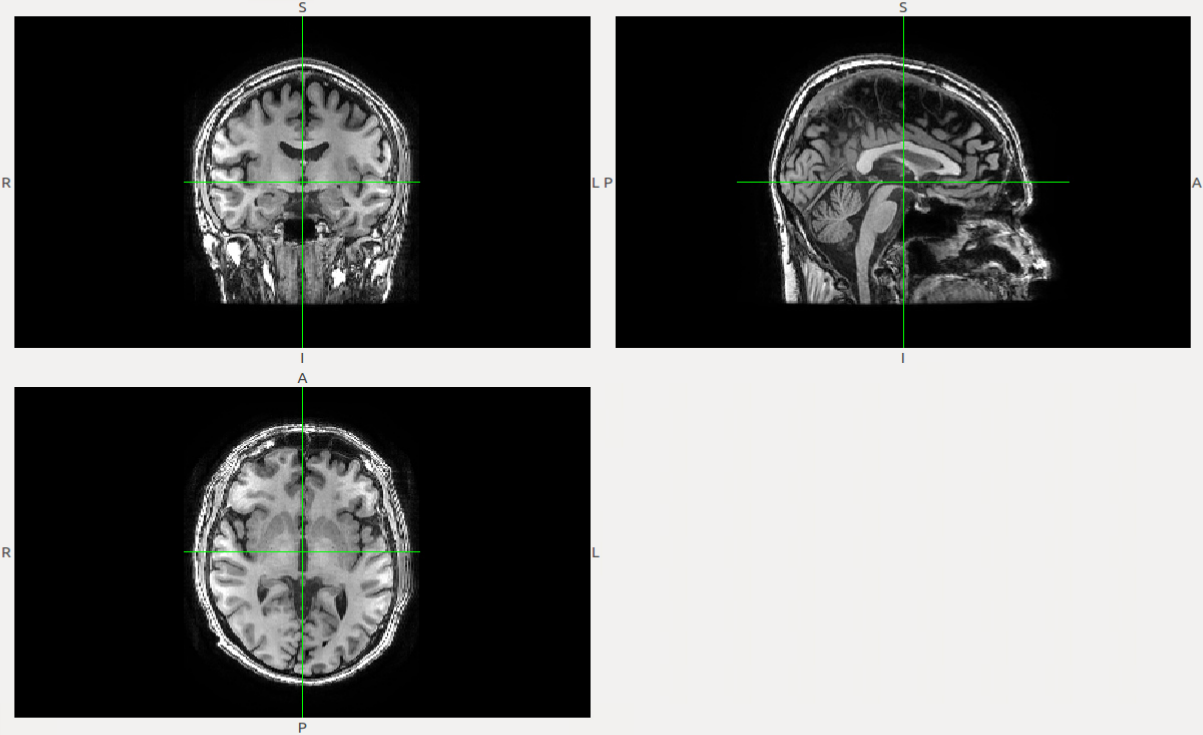

In this section, we present the experimental results of the different steps of the proposed CAD system to diagnose PD is presented. First, using FreeSurfer, the preprocessing step prepares the MRI data for the next steps. Fig.3 shows the MRI for subject 310231023102 and the resulting image after preprocessing.

Refer to caption

(a) Original MR image.

(b) Preprocessed MR image.

Figure 3: Preprocessing results for one of the subjects.